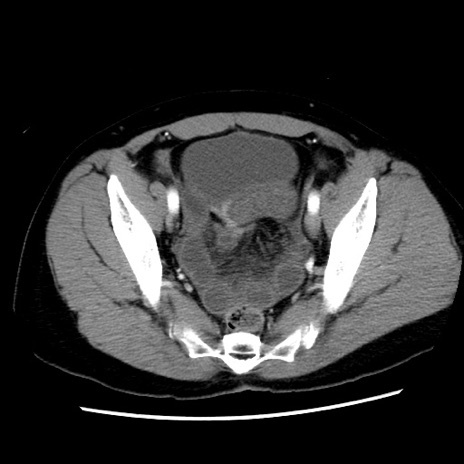

症例10(横断像)

【症例】 50歳代女性

【主訴】 腹痛

【現病歴】前日生レバーを食べた。今朝に排便あり。 昼前に突然発症の腹痛を生じ、当院救急外来を受診した。

【既往歴】 子宮筋腫にてで子宮全摘後

【身体所見】 意識清明、腹部:平坦、軟、下腹部やや左を中心に圧痛・反跳痛あり、筋性防御あり

【データ】WBC 7800、CRP 0.07